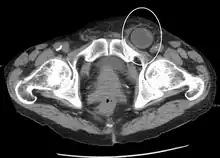

A physician may diagnose an inguinal hernia, as well as the type, from medical history and physical examination.[20] For confirmation or in uncertain cases, medical ultrasonography is the first choice of imaging, because it can both detect the hernia and evaluate its changes with for example pressure, standing and Valsalva maneuver.[21]

When assessed by ultrasound or cross sectional imaging with CT or MRI, the major differential in diagnosing indirect inguinal hernias is differentiation from spermatic cord lipomas, as both can contain only fat and extend along the inguinal canal into the scrotum.[22]

On axial CT, lipomas originate inferior or lateral to the cord, and are located inside the cremaster muscle, while inguinal hernias lie anteromedial to the cord and are not intramuscular. Large lipomas may appear nearly indistinguishable as the fat engulfs anatomic boundaries, but they do not change position with coughing or straining.[22]